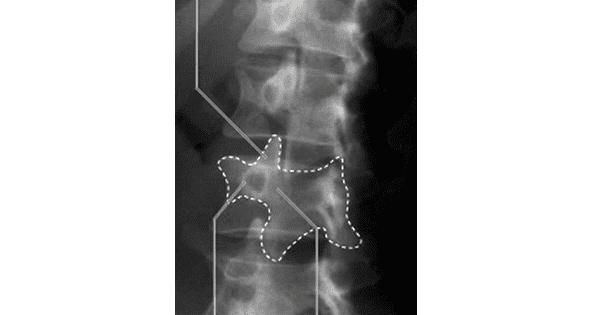

Following sign is seen in which condition?